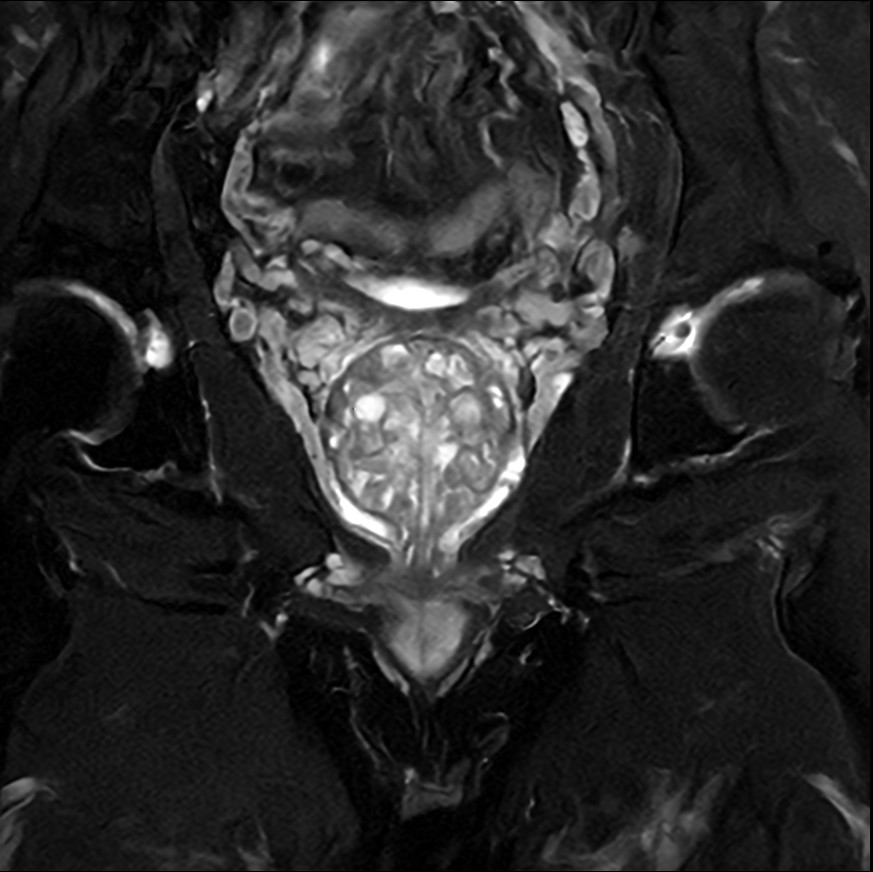

Fast Prostate imaging with SmartSpeed Precise

Kumamoto Chuo Hospital Japan

Used Solution